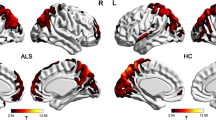

Compared with healthy controls, patients with ALS showed significant LGI reductions in the right occipital cortex (Fig. 1). No region with significantly higher LGI was observed in patients with ALS, relative to healthy controls. In the patient group, vertex-wise correlation analysis revealed a cluster in the left superior frontal gyrus where significant negative correlation was found between the LGI and disease duration (Fig. 2). No significant correlation was observed between LGI and ALSFRS-R in patients with ALS.

Statistical maps of the LGI differences between healthy controls and ALS patients. a Brain regions with cortical gyrification reductions in ALS. The results were corrected for multiple comparisons (P < 0.05, RFT-corrected). The color bar indicates the corrected P-values. b T-statistic of the corresponding between-group contrast (healthy controls-ALS patients)